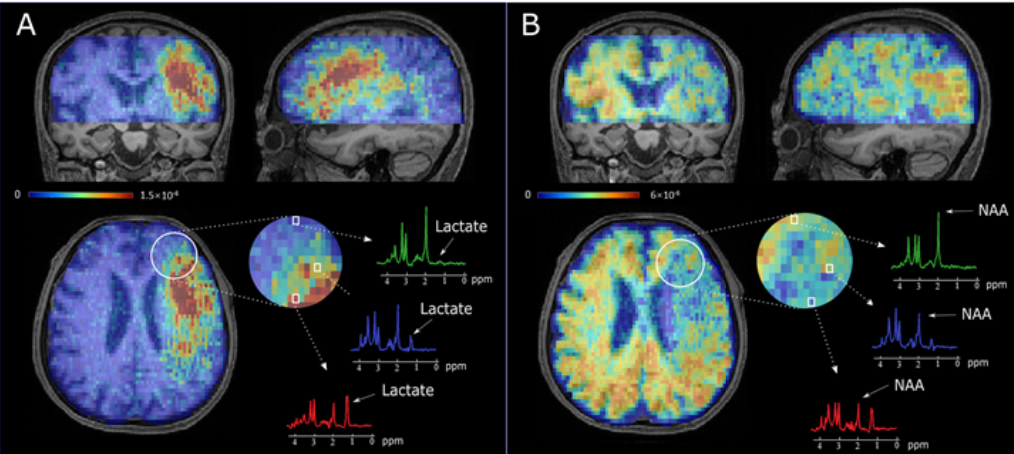

近日,williamhill威廉希尔官网李瑶课题组在急性脑卒中患者全脑高分辨率快速代谢成像方面取得了突破,首次实现8分钟内3毫米空间分辨率脑卒中患者全脑神经细胞代谢成像,获得NAA及乳酸等重要神经代谢物分布图谱。该研究以“Fast high-resolution metabolic imaging of acute stroke with 3D magnetic resonance spectroscopy”为题发表在脑科学研究领域权威期刊《Brain》上(DOI:10.1093/brain/awaa264),并被选为11月刊封面论文,且获得Brain Tweet的官方推送报道。

脑代谢改变是急性卒中脑组织损伤的重要特征,磁共振波谱成像技术(MRSI)可以实现无创在体脑代谢成像。但由于采集时间长、空间分辨率差、覆盖范围窄等不足,MRSI目前在临床上应用受到极大限制。李瑶课题组与美国UIUC的Zhi-Pei Liang教授团队积极合作,首次实现了SPICE(SPectroscopic Imaging by exploiting spatiospectral CorrElation)技术的脑卒中临床转化,在8分钟内即可获得空间分辨率为2 *3 *3mm3的N-乙酰天冬氨酸(NAA)和乳酸(Lactate)等重要神经代谢物的同步3D全脑影像,并对急性脑卒中缺血半暗带进行有效区分。该成果表明SPICE提供的神经代谢影像信息比传统的血流灌注成像对卒中后缺血组织的损伤程度提供更精准的判定,为进一步探究快速高分辨率磁共振代谢成像在急性脑卒中的临床应用提供了重要支持。